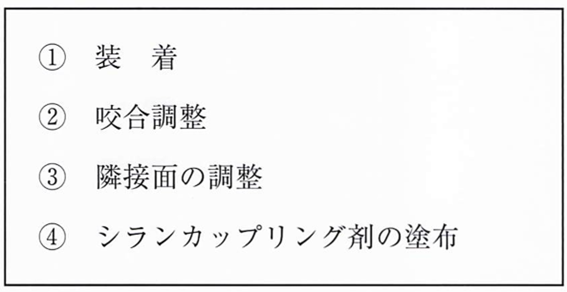

午前-40

54歳の女性。下顎左側第二小臼歯の冷水痛を主訴として来院した。 噴合面および遠心面にう蝕を認めたため修復処置が行われることになった。製作した修復物の写真と装着時の操作内容を別に示す。 操作内容で3番目に行うのはどれか。1つ選べ。

a. ①

b. ②

c. ③

d. ④

解答を見る

a